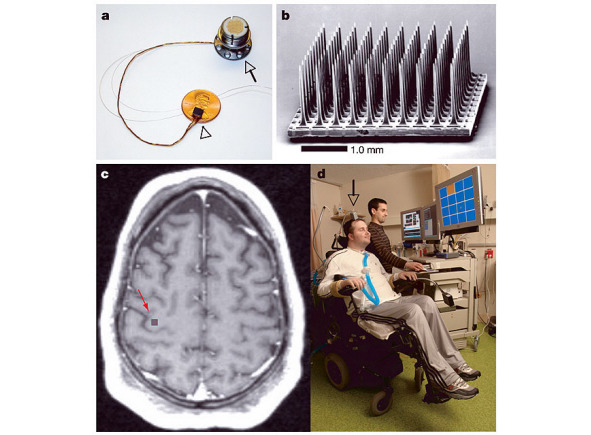

Другим из самых известных и самых продвинутых специалистов в области нейроинтерфейсов является американец венгерского происхождения Эндрю Шварц (Andrew Shwarz) (рис. 3). В рамках специального проекта DARPA Министерства обороны США Э. Шварц ведет разработку имплантируемого интерфейса «мозг  компьютер» с объемом финансирования в 500 млн долл. США. Программа шла 5 лет на обезьянах и уже несколько лет идет на людях (рис. 4). Основной принцип информационного подключения к мозгу человека эта команда пытается осуществить путем имплантации в кору головного мозга решетки из микроэлектродов и попытки снятия внутримозгового сигнала из нервной ткани и создания роботизированного устройства самообслуживания инвалида и программного обеспечения для него путем управления его мыслями (рис. 5).

По данным этой команды разработчиков, им удалось «зарегистрировать моторный внутримозговой сигнал» с прецентральной извилины головного мозга, куда была имплантирована решетка микроэлектродов. Более того, полученный управляющий сигнал удалось не только зарегистрировать в моторных центрах коры головного мозга, но и «послать его обратно». Исследователи из Питтсбурга (США) пришли к выводу, что мыслительными командами пациент-инвалид якобы способен управлять самостоятельно «силой мысли» и выполнять простые моторные действия роботизированным устройством после небольшого периода обучения. Проф. Andrew Shwarz, очень увлеченный и талантливый ученый-нейробиолог,  человек, который верит в то, что он делает, но реальных результатов он также не может представить, и это, на наш взгляд, связано не с только с проблемой нейрофизиологии и нейробиологии, сколько с устаревшей методологией оценки информационной составляющей работы мозга во всем мировом научном процессе нейронаук и с крайне сложным и высокотехнологичным математическим и компьютерным обеспечением подобной работы. Нам показалось, что уникальное математическое программное обеспечение этих исследований в лаборатории проф. Эндрю Шварца значительно превосходит современные познания и научные представления в понимании нейрофизиологии работы мозга человека, и оно само доделывает и додумывает то, что головной мозг неспособен предоставить для обработки и анализа. В целом работа математиков и программистов этой группы достойна уважения и восхищения!

Рис. 5. Научное понимание группы проф. Эндрю Шварца о принципах снятия и регистрации полученной от мозга информации, а также локализация электродов в мозге исследуемого человека